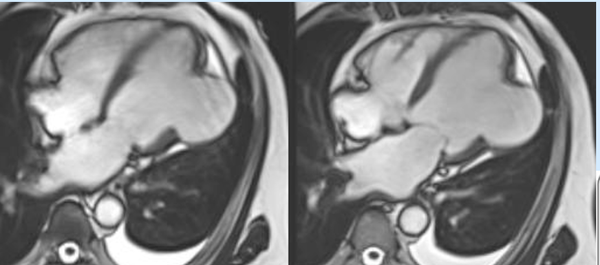

COD 077 - Decoding Septum Predominant Hypertrophic Cardiomyopathy

Understanding standard septum predominant HCM